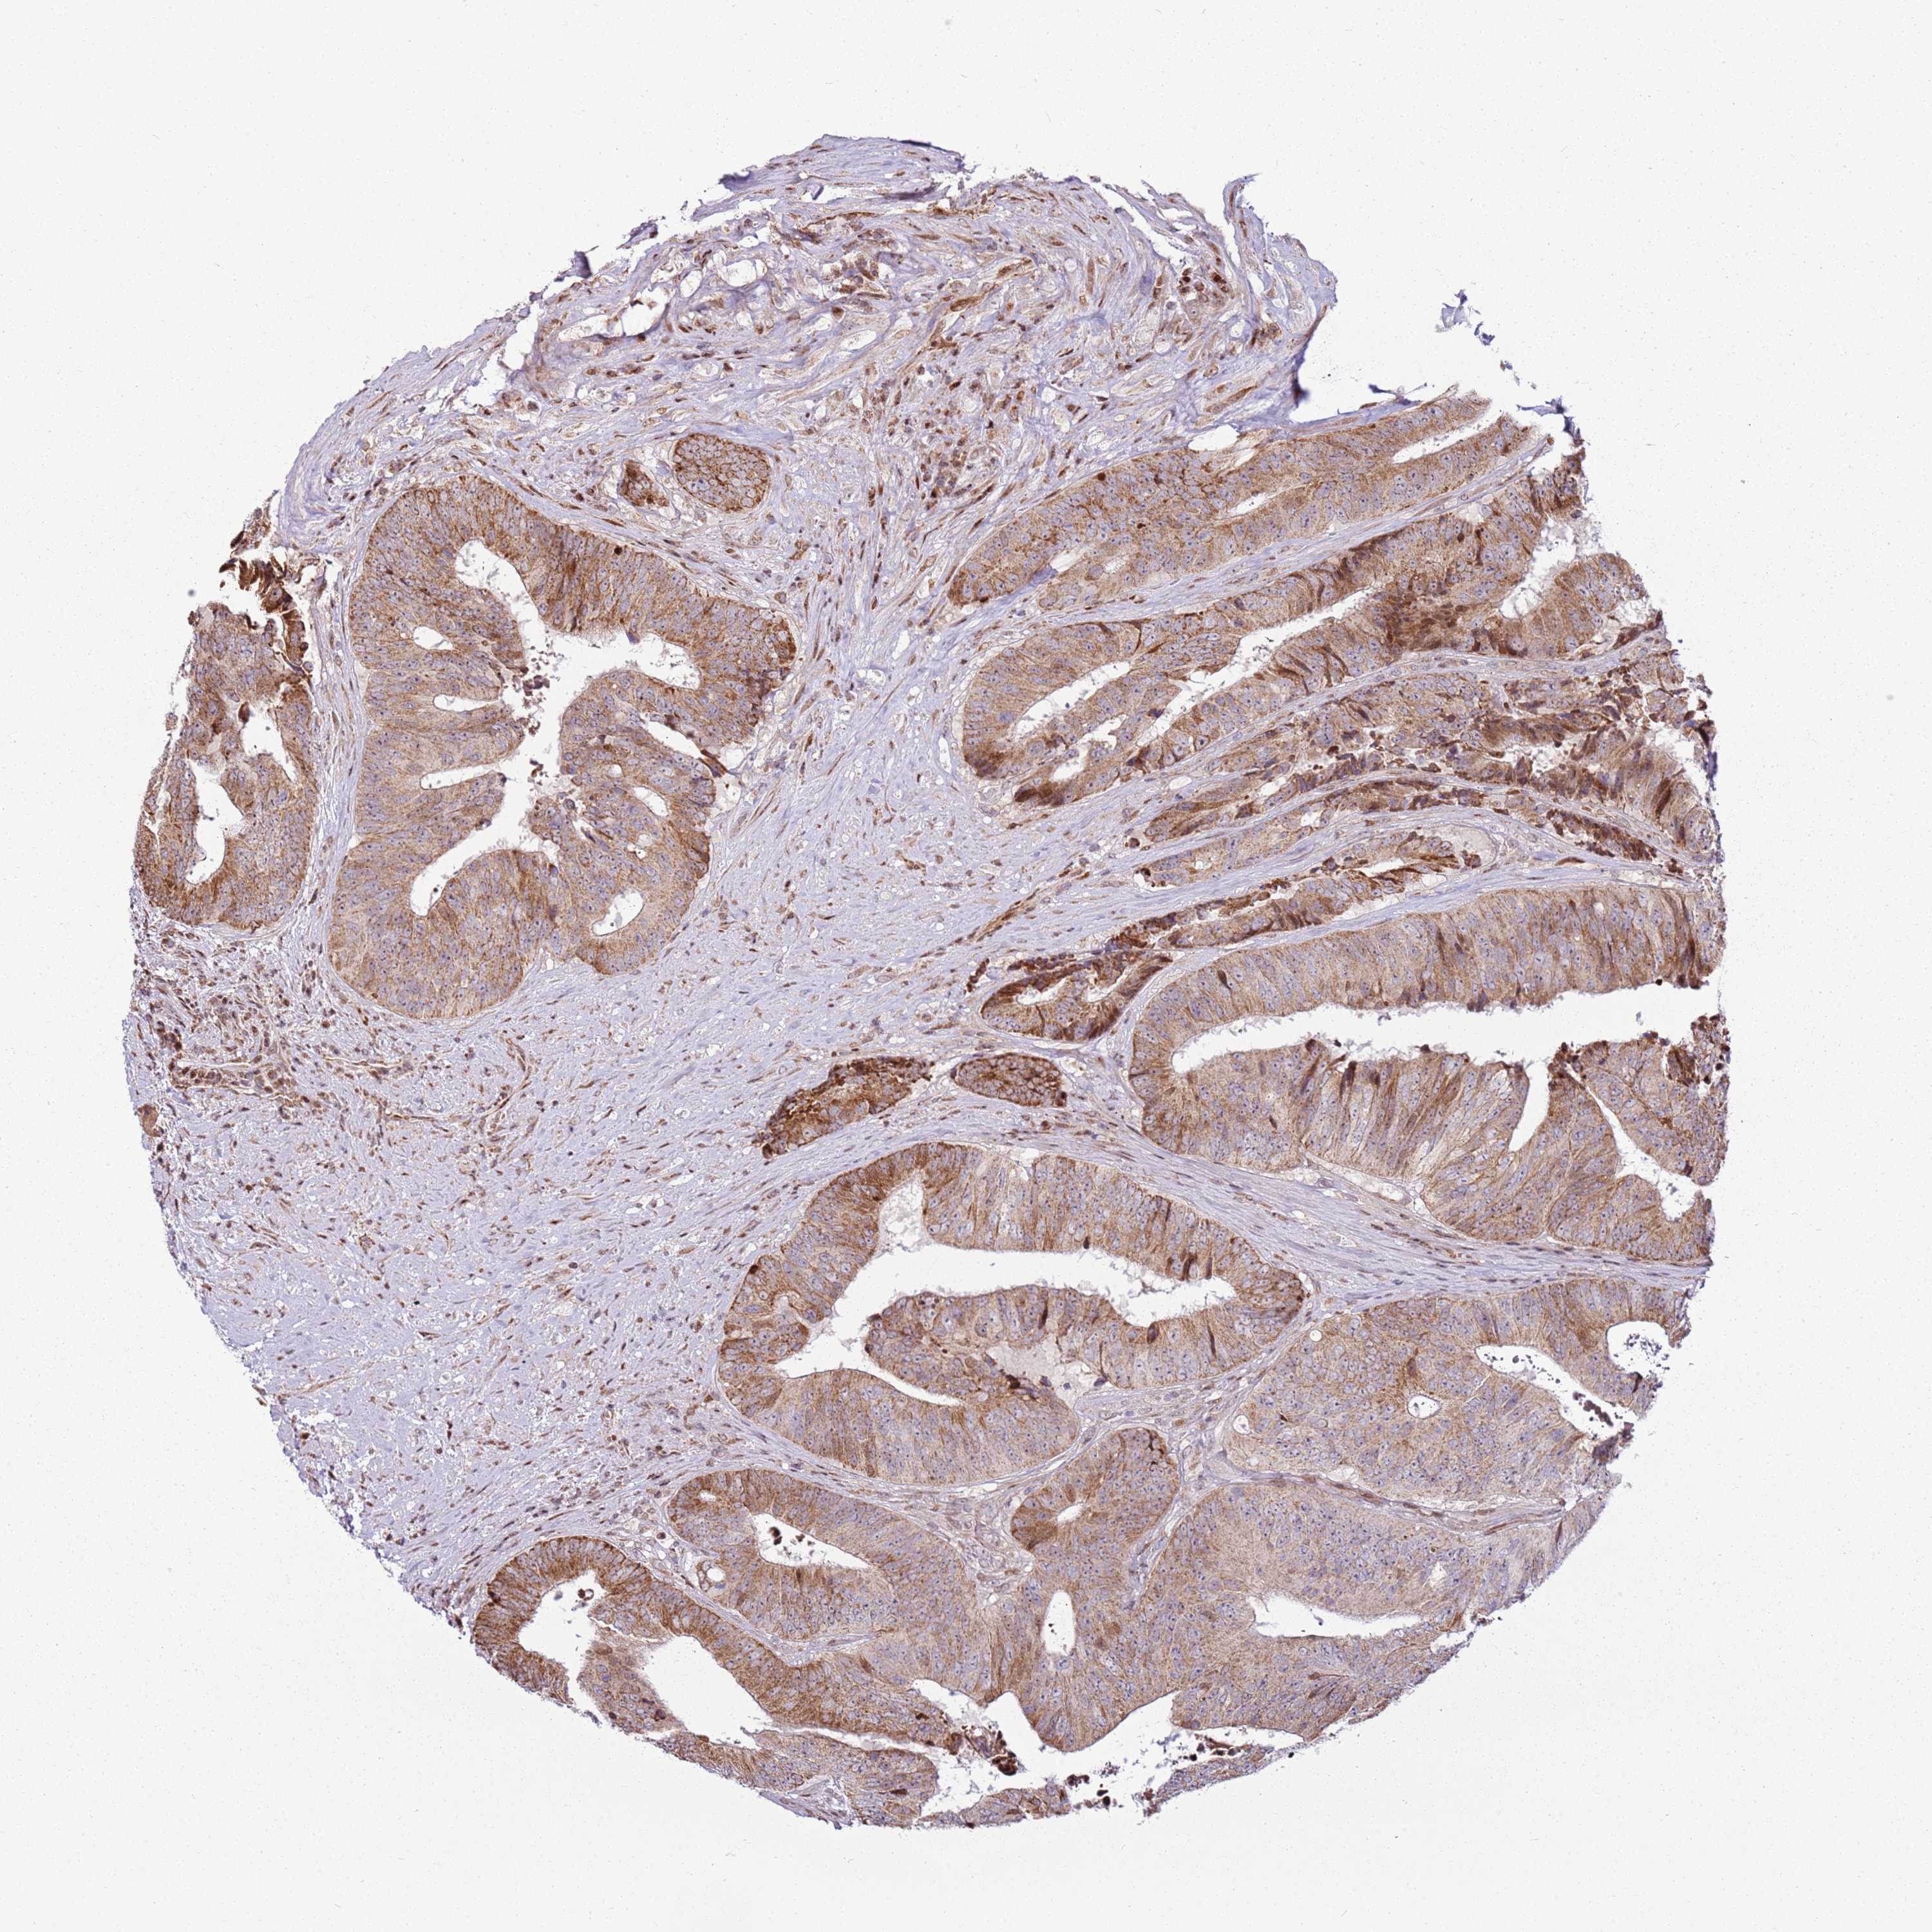

CANCER COLORECTAL CANCER Show tissue menu

Colorectal cancer

Human cancer

Colon adenocarcinoma